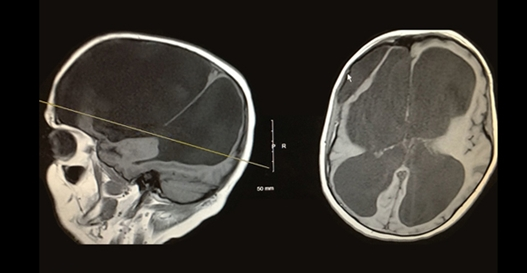

脑积水是如何诊断的?脑积水是通过临床神经病学评估和使用头颅成像技术来诊断的,例如超声波检查法计算机断层摄影,磁共振成像或者压力监测技术。医生根据个人的年龄、临床表现以及已知或怀疑的大脑或脊髓异常的存在来选择合适的诊断工具。